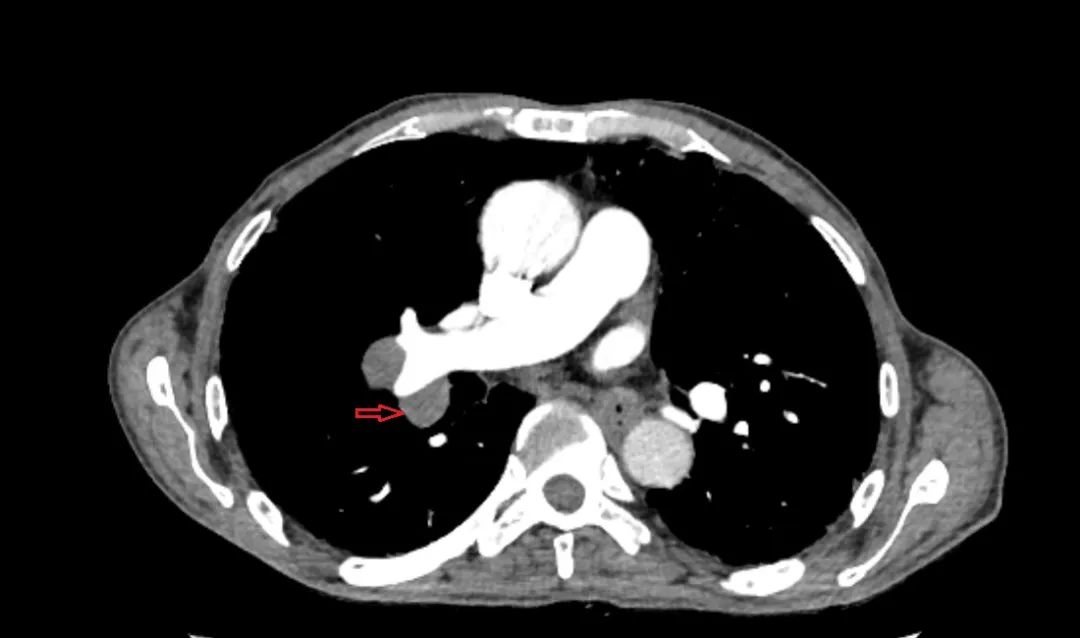

病例一

患者胸部增强CT提示右下肺不规则囊腔,并纵隔、右肺门淋巴结肿大,最大者短径15mm,且紧邻血管。患者肺功能差、心率快,于全麻下成功穿刺取得组织确诊腺癌,术中出血约10ml,术后患者无感明显不适。